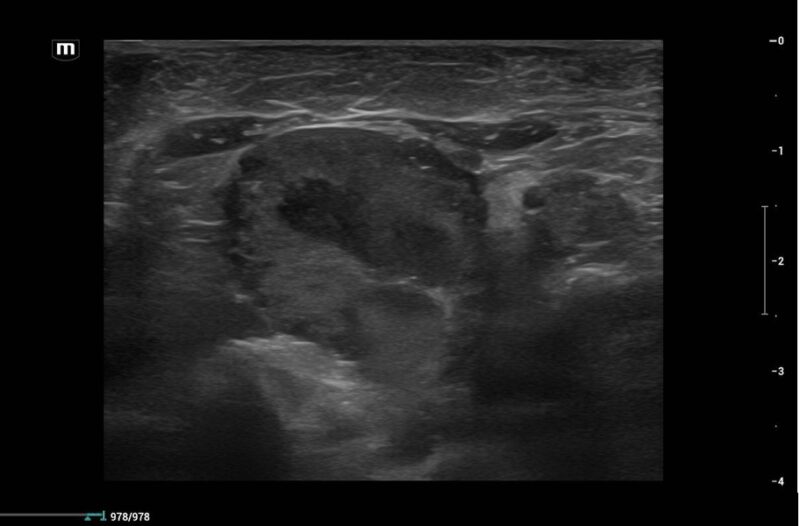

Eine zentrale Rolle spielt die bildgebende Diagnostik. Das Abdomenröntgen sollte immer in zwei Ebenen durchgeführt werden, um Beckenengstände oder alte Traumata sicher beurteilen zu können. Zur Diagnostik eines Megakolons wird der Kolondurchmesser mit der Länge des Wirbelkörpers von L7 verglichen. Ein Durchmesser von mehr als dem 1,5-fachen der L7-Länge gilt als zuverlässiger Hinweis auf ein Megakolon. Ultraschall kann strukturelle Veränderungen wie Entzündungen oder Neoplasien darstellen. Eine Kolonoskopie ist selten erforderlich, kann aber bei Strikturen oder intraluminalen Massen hilfreich sein. Bei neurologischen Auffälligkeiten können weiterführende Untersuchungen wie CT oder MRT notwendig werden.